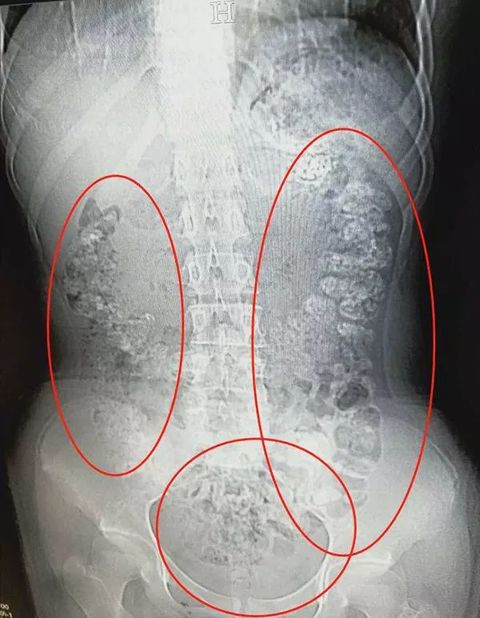

top000緊急入院の14歳少女 胃から肛門までタピオカ100個発見!中国・浙江省

若い女性の間で人気沸騰中のタピオカミルクティー。1990年代、2000年代のふたつのブームを経て、現在は第3次ブームと言われるほど、毎日のように新しい店が誕生しているが、中国・浙江省では先月、14歳の女の子が腹痛を訴えて緊急入院した。

何日間も排便がなく、腹部CTスキャン検査を実施した結果、胃から腸、肛門まで100個以上のタピオカパールが数珠つなぎに詰まっていたという!

地元メディア「掌上紹興(シャオシン・ニュース)」の報道によると、浙江省中部の地方都市、諸曁(しょき)市に住む14歳の女の子、小沈(シャオシェン)は先月28日、猛烈な腹痛を訴えて、人民病院に救急搬送された。